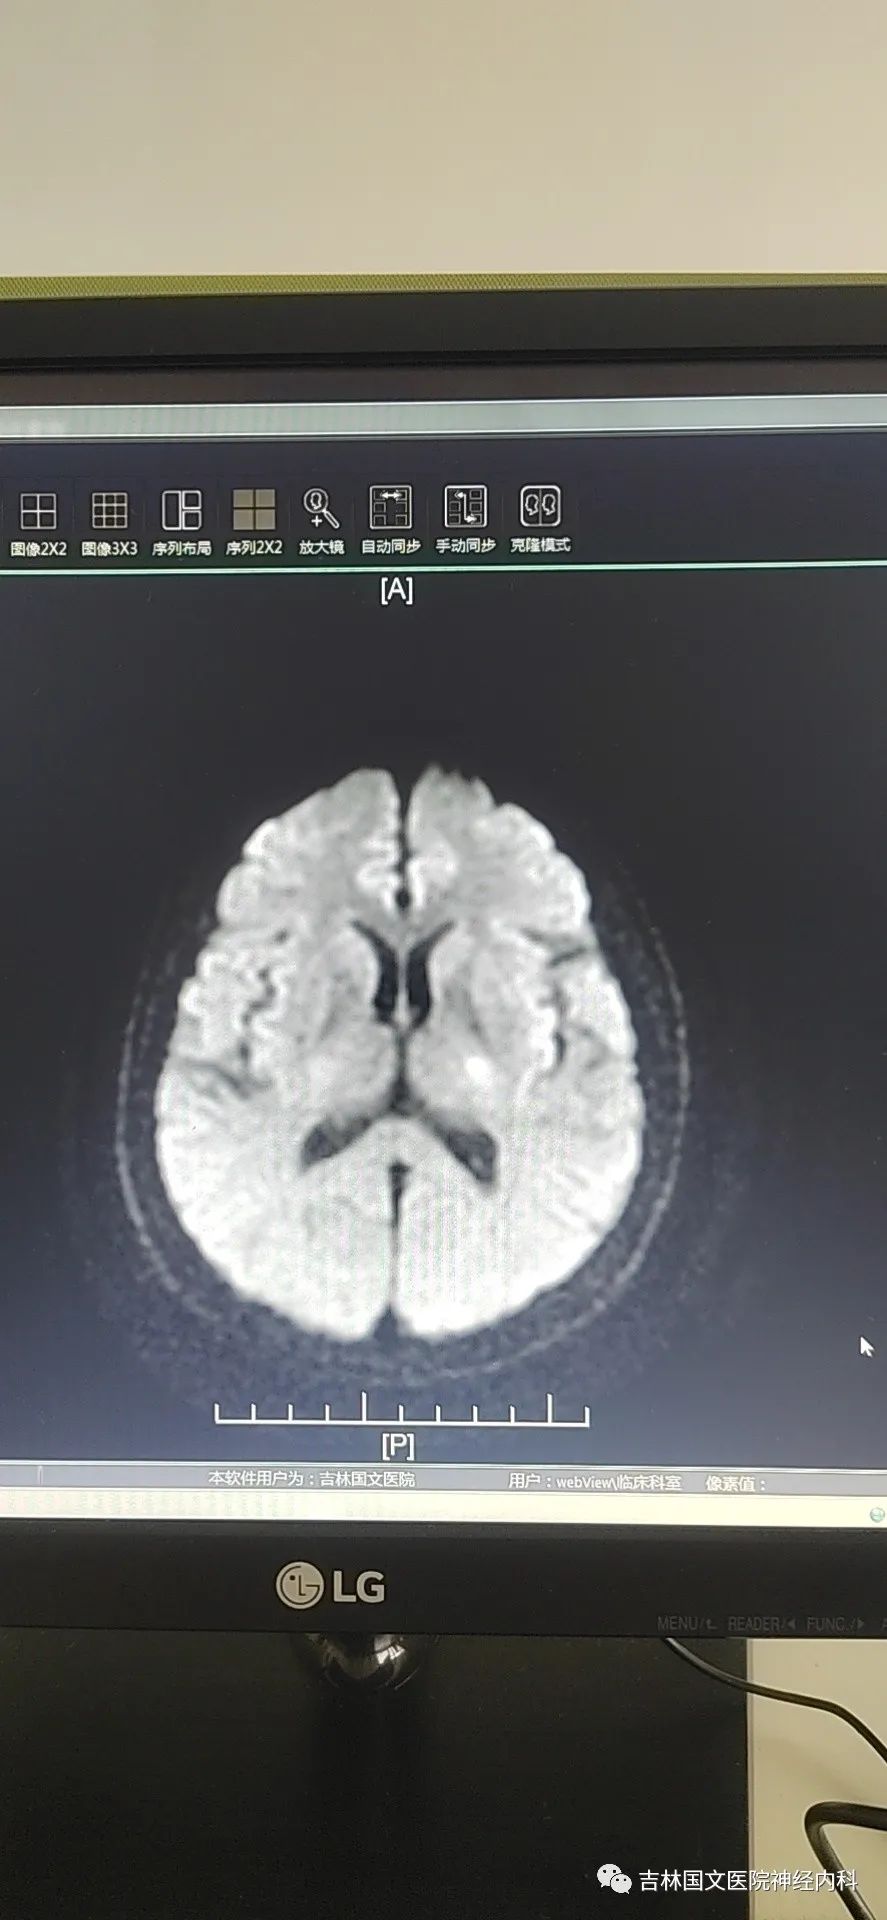

到達急診后,立即啟動“卒中綠色通道”,行頭CT檢查后直入療區(qū)。

入療區(qū)后患者癥狀完全緩解,立即給予心電監(jiān)護,急采血,查體:血壓174/93mmHg,血氧飽和度99%。神志清楚,言語流利,雙側(cè)鼻唇溝對稱,伸舌居中,四肢肌力5級,肌張力正常,雙側(cè)膝腱反射對稱存在,雙側(cè)Babinski征(-)。同時頭部CT結(jié)果回報未見顱內(nèi)出血。